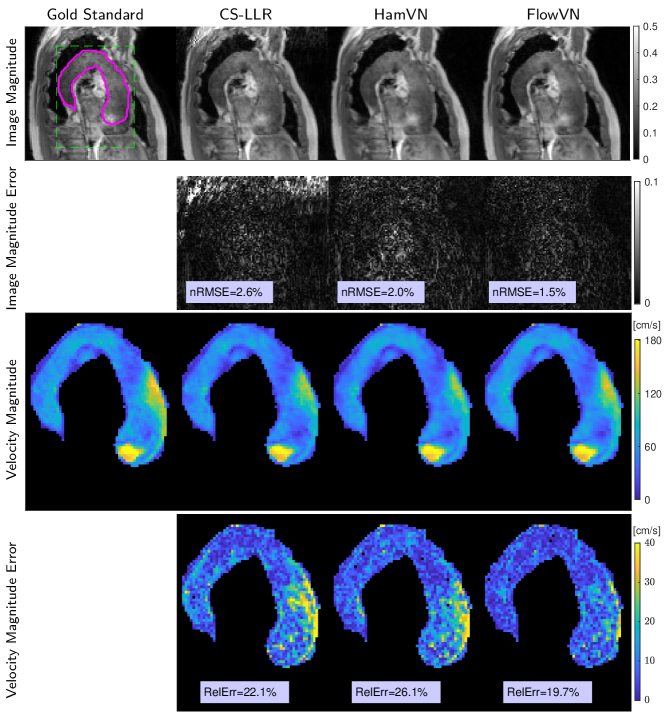

Fig. 4 indicates that FlowVN can accurately reconstruct the jet at the inlet section of the aorta for a patient with a pathological aortic valve.

To evaluate reconstruction accuracy on pathological anatomy, 4D flow data was acquired in a single patient with dilation of the ascending aorta, combined aortic stenosis and regurgitation due to a bicuspid aortic valve on a 3T Philips Ingenia system (Philips Healthcare, Best, the Netherlands) using a navigator-gated 2-fold accelerated parallel imaging 5 scan.